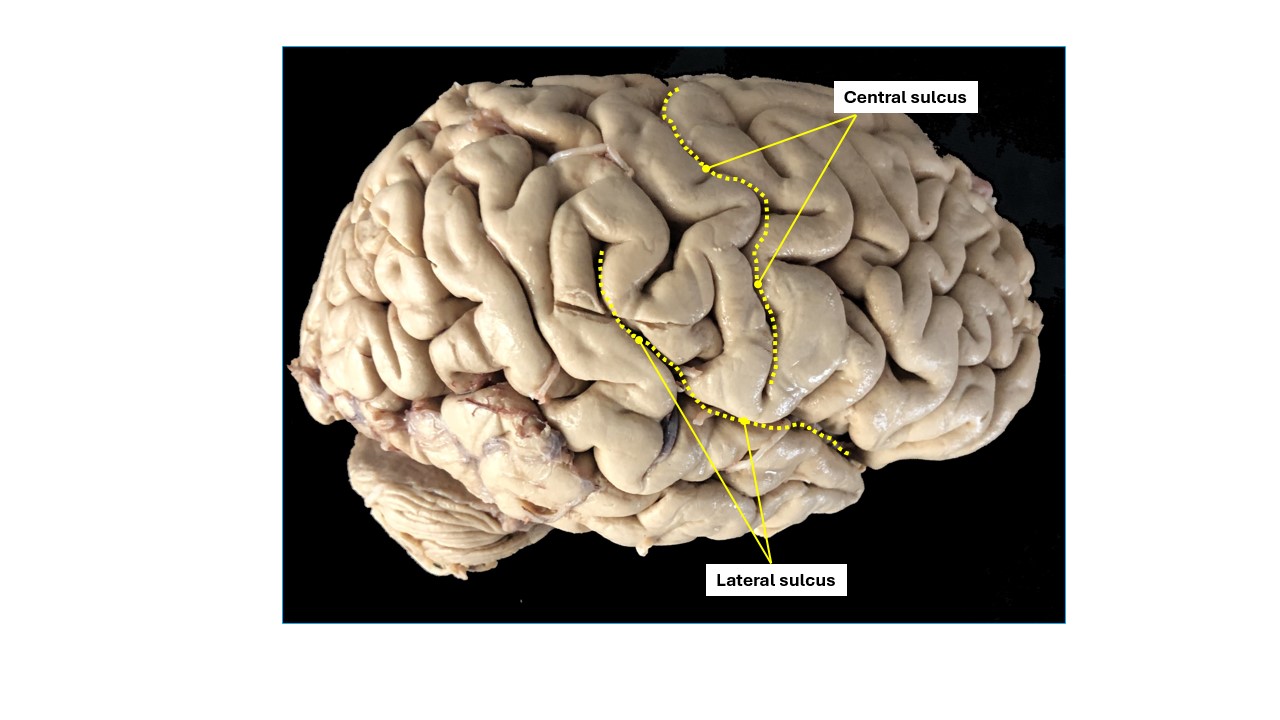

Recall that the surfaces of the cerebrum, and therefore the lobes, have a distinct topography that is formed by the sulci and gyri.

Sulci/fissures of the cerebrum

Identify the sulci/fissures of the cerebrum on a brain.

Longitudinal, a.k.a. sagittal fissure/sulcus:Â Separating the two cerebral hemispheres

Lateral sulcus (Sylvian fissure):Â Separating temporal lobe from parietal and frontal lobe

Central sulcus:Â Separating the frontal and parietal lobes